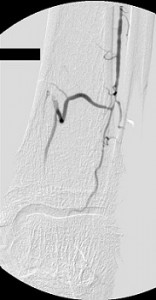

The images in the top panel illustrate multicentric moderate and severe (>50%) narrowings of the proximal left common femoral artery (LCFA) – not shown – and the superficial femoral artery and a focal critical stenosis of the proximal left tibioperoneal trunk in an elderly diabetic man with a chronic ulcer of his left foot. Notice that the critical tibioperoneal stenosis limits blood flow into the patient’s only named branch of his left popliteal artery, the peroneal artery, which is the principal path of blood inflow to the foot. Note, too, the severity of the lack of perfusion of the foot as shown by the “whiteness” of the patient’s hind foot.